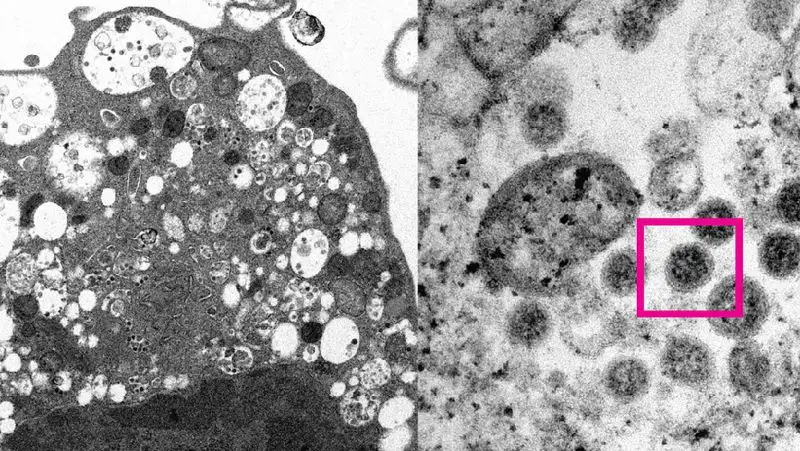

Группа ученых из Вашингтонского, Висконсинского и Токийского университетов провела эксперименты на мышах и хомяках, чтобы выяснить влияние «омикрон-штамма» на организм, передает Zakon.kz.

Как пишет lenta.ru, выяснилось, что «омикрон-штамм» поражает в основном верхние дыхательные пути – нос и носоглотку, а на легкие распространяется значительно реже, чем другие варианты COVID-19.

Животные, зараженные «омикрон-штаммом», в среднем испытывали более легкие симптомы болезни и реже сталкивались с потерей веса. Другие варианты коронавирусной инфекции могли вызывать рубцы в легких и серьезное затруднение дыхания.